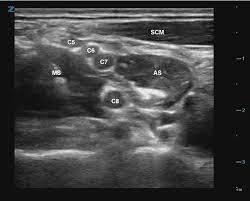

So when you are looking at 3-5 black circles in the interscalene groove, how do you differentiate which ones are C5, C6, C7 vs. multiples coming off the same root? For example how do we know in the picture below that we are not looking at C5, C6, C6, C7 (or any other anatomical variant).

So when you are looking at 3-5 black circles in the interscalene groove, how do you differentiate which ones are C5, C6, C7 vs. multiples coming off the same root? For example how do we know in the picture below that we are not looking at C5, C6, C6, C7 (or any other anatomical variant).